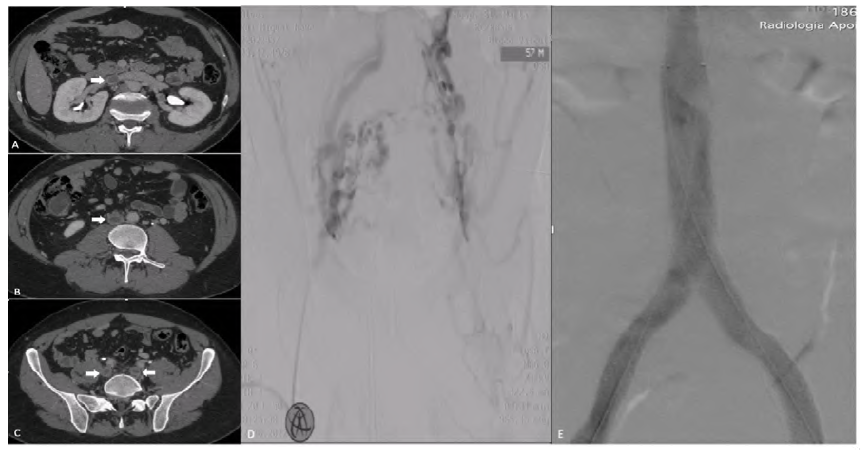

A 45-year-old patient with a previous unprovoked ilio-caval deep venous thrombosis (A,B,C, arrows) and severe post-thrombotic syndrome (long-lasting active venous ulcers, bilaterally) underwent ilio-caval stenting. The initial venography confirmed chronic total occlusion of both iliac veins and the infrarenal inferior vena cava with exuberant pelvic collaterals (D). The iliac occlusions were crossed using an HT Command 0.018 [Abbott®] and standard 0.035 hydrophilic [Terumo®) guidewires and predilated with a 10mm non-compliant balloon. Ilio-caval reconstruction was performed using the confluence technique, with a Sinus XL stent (Optimed®) 20x100mm in the inferior vena cava and Sinus Venous stents (Optimed®) 16x120mm and 14x120mm extending from the iliac vein confluence to the common femoral veins, with an excellent angiographic result (E). Complete venous ulcer healing was observed within two months. Deep venous recanalization has a role in the management of severe post-thrombotic syndrome due to ilio-caval obstruction.(Figure 1)